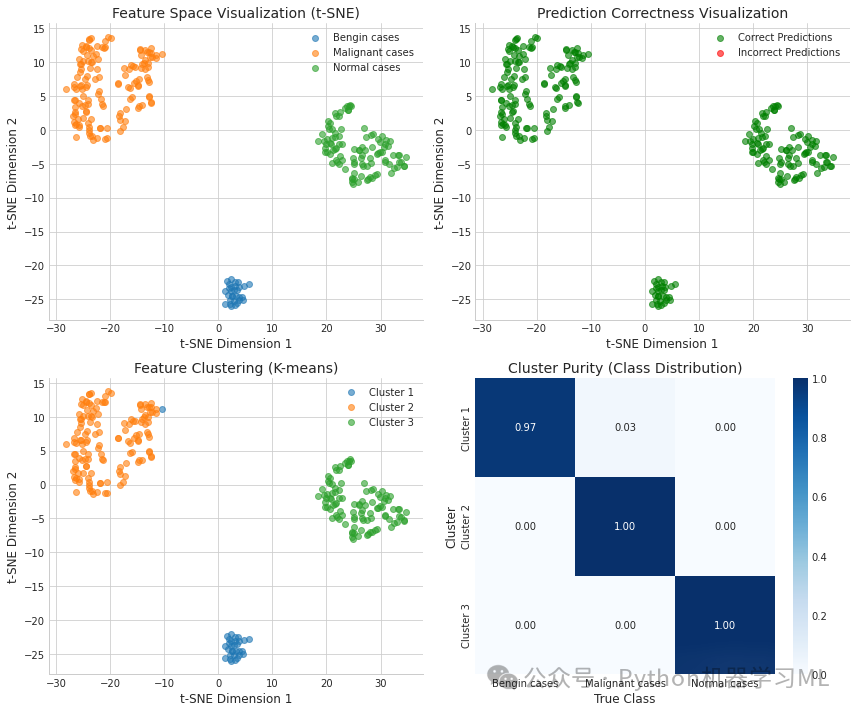

第二阶段:特征可视化和聚类分析

这部分代码提取深度学习模型的特征表示,并通过降维和聚类分析探索数据结构与模型表现之间的关系。

python# 导入特征可视化和聚类分析所需的库

from sklearn.decomposition import PCA # 导入主成分分析用于降维

from sklearn.manifold import TSNE # 导入t-SNE用于高维数据可视化

from sklearn.cluster import KMeans # 导入K均值聚类

defvisualize_features(model, X, y, categories, layer_name=-2):

"""

提取和可视化指定层的特征

参数:

model: 深度学习模型

X: 输入数据

y: 标签数据

categories: 类别名称列表

layer_name: 要提取特征的层索引,默认为倒数第二层

返回:

原始特征、PCA降维特征、t-SNE降维特征和聚类标签

"""

# 创建一个模型,输出指定层的特征

feature_model = tf.keras.models.Model(

inputs=model.input,

outputs=model.layers[layer_name].output

) # 创建一个新模型,使用原模型输入,输出指定层的激活值

# 提取特征

features = feature_model.predict(X) # 使用特征模型提取特征

# 应用降维进行可视化

# 先使用PCA减少计算时间

if features.shape[1] > 50: # 如果特征维度大于50

pca = PCA(n_components=50) # 创建PCA对象,设置降维至50维

features_pca = pca.fit_transform(features) # 应用PCA降维

print(f"PCA explained variance ratio: {sum(pca.explained_variance_ratio_):.4f}") # 打印PCA解释方差比例

else: # 如果特征维度不大于50

features_pca = features # 不使用PCA降维

# 然后使用t-SNE进行可视化

tsne = TSNE(n_components=2, random_state=42, perplexity=min(30, len(X)//10)) # 创建t-SNE对象,设置降至2维,固定随机种子,动态设置困惑度

features_tsne = tsne.fit_transform(features_pca) # 应用t-SNE降维

# 绘制t-SNE可视化结果

plt.figure(figsize=(12, 10)) # 创建12x10大小的图形

# 根据真实类别绘制

plt.subplot(2, 2, 1) # 创建2x2网格的第1个子图

for i, category inenumerate(categories): # 遍历每个类别

indices = np.where(y == i)[0] # 获取属于当前类别的样本索引

plt.scatter(features_tsne[indices, 0], features_tsne[indices, 1], label=category, alpha=0.6) # 绘制散点图

plt.title('Feature Space Visualization (t-SNE)') # 设置标题

plt.xlabel('t-SNE Dimension 1') # 设置x轴标签

plt.ylabel('t-SNE Dimension 2') # 设置y轴标签

plt.legend() # 添加图例

# 根据预测正确性绘制

plt.subplot(2, 2, 2) # 创建2x2网格的第2个子图

y_pred = np.argmax(model.predict(X), axis=1) # 获取预测类别

correct = (y_pred == y) # 判断预测是否正确

plt.scatter(features_tsne[correct, 0], features_tsne[correct, 1],

label='Correct Predictions', color='green', alpha=0.6) # 绘制预测正确的点

plt.scatter(features_tsne[~correct, 0], features_tsne[~correct, 1],

label='Incorrect Predictions', color='red', alpha=0.6) # 绘制预测错误的点

plt.title('Prediction Correctness Visualization') # 设置标题

plt.xlabel('t-SNE Dimension 1') # 设置x轴标签

plt.ylabel('t-SNE Dimension 2') # 设置y轴标签

plt.legend() # 添加图例

# K均值聚类

n_clusters = len(categories) # 聚类数量设为类别数量

kmeans = KMeans(n_clusters=n_clusters, random_state=42, n_init=10) # 创建K均值聚类对象

cluster_labels = kmeans.fit_predict(features_pca) # 应用K均值聚类

# 根据聚类结果绘制

plt.subplot(2, 2, 3) # 创建2x2网格的第3个子图

for i inrange(n_clusters): # 遍历每个聚类

indices = np.where(cluster_labels == i)[0] # 获取属于当前聚类的样本索引

plt.scatter(features_tsne[indices, 0], features_tsne[indices, 1],

label=f'Cluster {i+1}', alpha=0.6) # 绘制散点图

plt.title('Feature Clustering (K-means)') # 设置标题

plt.xlabel('t-SNE Dimension 1') # 设置x轴标签

plt.ylabel('t-SNE Dimension 2') # 设置y轴标签

plt.legend() # 添加图例

# 计算聚类纯度

purity_table = np.zeros((n_clusters, len(categories))) # 创建纯度表格

for i inrange(n_clusters): # 遍历每个聚类

cluster_indices = np.where(cluster_labels == i)[0] # 获取属于当前聚类的样本索引

for j inrange(len(categories)): # 遍历每个类别

purity_table[i, j] = np.sum(y[cluster_indices] == j) / len(cluster_indices) iflen(cluster_indices) > 0else0# 计算聚类中每个类别的比例

# 将聚类纯度绘制为热图

plt.subplot(2, 2, 4) # 创建2x2网格的第4个子图

sns.heatmap(purity_table, annot=True, fmt='.2f', cmap='Blues',

xticklabels=categories, yticklabels=[f'Cluster {i+1}'for i inrange(n_clusters)]) # 绘制热图

plt.title('Cluster Purity (Class Distribution)') # 设置标题

plt.ylabel('Cluster') # 设置y轴标签

plt.xlabel('True Class') # 设置x轴标签

plt.tight_layout() # 调整布局

plt.show() # 显示图形

# 返回特征和降维结果

return features, features_pca, features_tsne, cluster_labels # 返回原始特征、PCA降维特征、t-SNE降维特征和聚类标签

# 提取和可视化特征(取消注释以运行)

features_data = visualize_features(model3, X_valid, y_valid, categories) # 调用特征可视化函数

-

特征可视化和聚类分析:

-

- 提取模型内部特征表示,通过PCA和t-SNE进行降维可视化

- 从多个角度分析特征空间:真实类别分布、预测正确性和聚类结构

- 通过K均值聚类探索数据的内在结构,并分析聚类纯度

- 帮助理解模型决策边界和潜在的特征学习质量